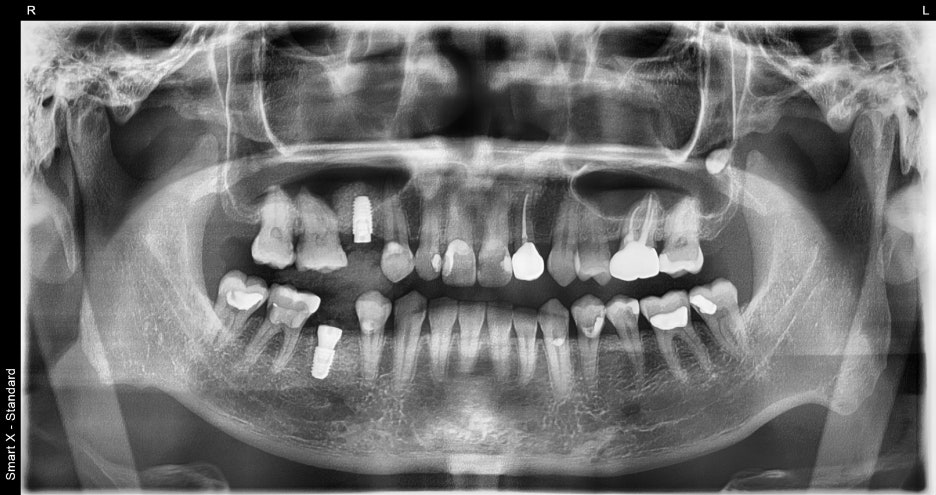

① 발치 및 임플란트 식립

– 깨진 치아를 발치한 뒤, 잇몸뼈 상태를 확인하고

바로 임플란트를 심었습니다.

② 임플란트 식립

– 결손 부위에도 동시에 임플란트를 진행했습니다. 뼈 상태가 좋아 추가 시술 없이 안정적으로

식립이 가능했습니다.

④ 최종 보철물 장착

– 원내 기공소에서 환자분의 교합과 치아 색상에 맞춘 지르코니아 크라운을 제작해 장착했습니다. 장착 후 교합 조정을 통해 양쪽 씹는 힘을 고르게 분산시켰습니다.

치료 요약

1회차: #45 발치 + 즉시 임플란트,

#15 임플란트 동시 식립

2~3회차: 치유 및 골유착 과정 점검

4회차: 최종 보철물 장착

→ 총 약 3개월 소요, 4회 내원으로 완성